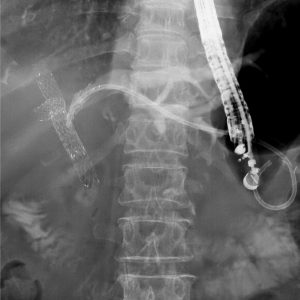

重症急性膵炎後のWONに対するEUS下膿瘍ドレナージ